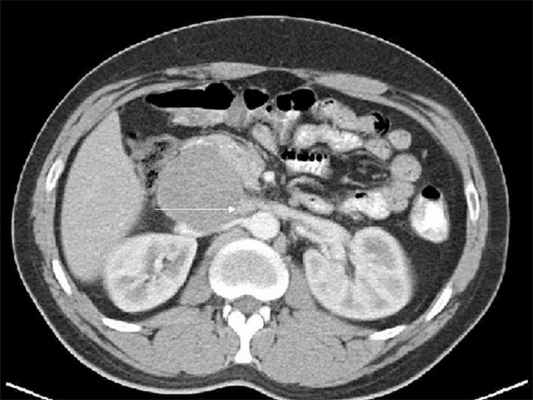

• КТ: дольчатое мягкотканное образование низкой плотности:

о Крупные, рыхлые кальцификаты встречаются в 30% случаев

Ультразвуковая эхография помогает определить размеры и глубину расположения опухоли, выяснить ее связь с сосудами; компьютерная томография позволяет определить опухоли диаметром начиная с 1,5-2,0 см, точное их распространение, топографию, обнаружить увеличение лимфатических узлов.